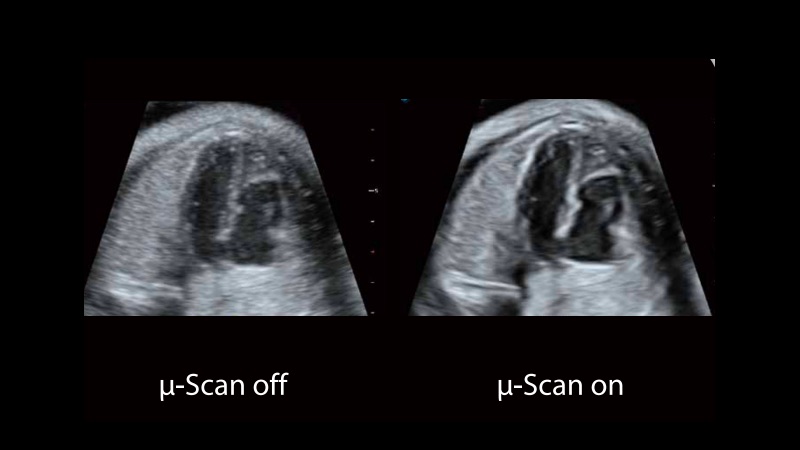

μ-Scan+新一代微米成像技術(shù)

新一代微米成像技術(shù)大大提高了器官和病變的可見性。高清對(duì)比度分辨率將抑制斑點(diǎn)噪聲,同時(shí)保持真實(shí)的組織結(jié)構(gòu)。